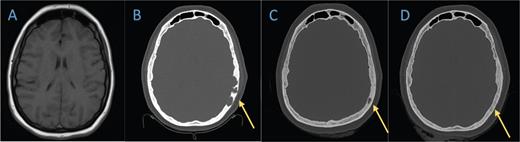

Axial bone window of (B) the head CT in February 2021 shows lytic lesions in the left temporal cranium that is not present on A) the brain MRI from 2019. C) Head CT in November 2021 demonstrates marked improvement of the lytic process. D) The last head CT obtained in July 2022 shows near resolution of the known lesion. palliative care. Early referral for psychological support and symptom management has been a beneficial strategy in many patients.7